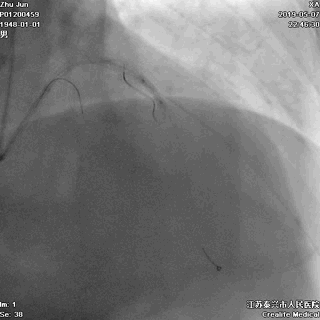

三、球囊扩张病变

---打通生命通道

前降支至左主干行PTCA